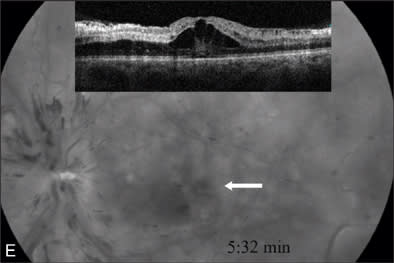

At our initial examination in August 2008, corrected visual acuity was 20/30 in the right eye and 20/50 in the left, with normal ocular pressure in both eyes. There were no rubeosis irides in either eye. Fundus examination appeared normal in the right eye while the left eye revealed a typical nonischemic CRVO (Figure 1A). Fluorescein angiography of the left eye (Figure 1B to 1E) showed generalized dilated, tortuous retinal veins, intraretinal hemorrhages, peripheral retinal non-perfusion areas, and microvascular leakage at the macula (Figure 1E, arrow). Despite the peripheral retinal ischemia, the macula itself was not ischemic at the first visit, as evidenced by the early phase FA showing 2 cilioretinal arteries supplying the fovea (Figure 1C, arrow). Spectral domain OCT (OPKO-OTI, Miami, FL.) confirmed the diagnosis of cystoid macular edema (CME). The patient got intravitreal bevacizumab (Avastin) injection (1.25 mg/0.05 mL) at the first visit.

Figure 1 A–G |